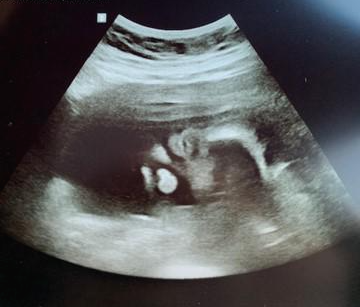

겸사겸사 걱정됐던 경부길이도 확인하고, 초음파로 쑥쑥이의 모습도 확인.

크리스마스 맞이 윙크(실눈)를 공개한 쑥쑥이 :-)

코에서 내가, 눈에서 그녀가 보이나 싶다.